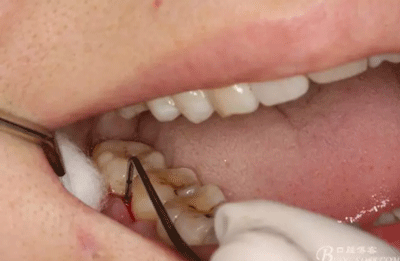

圖3.術(shù)前口內(nèi)影像情況:48頰側(cè)牙齦紅腫。照片有點曝光過度。不理想。

圖4.術(shù)前47遠(yuǎn)中探針檢查,遠(yuǎn)中牙周袋8mm